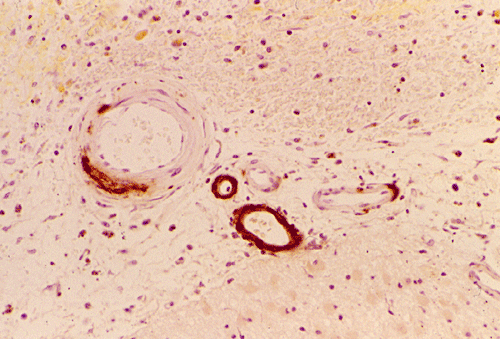

Histopathology: The hemorrhage, not surprisingly, is composed of blood (Panel B). At the periphery of the hemorrhage are areas that are heavily infiltrated by macrophages accompanied by substantial hemosiderin depositions (Panel C). On medium magnification, the blood vessel walls seems to be thickened and some ill-defined deposition are present in the wall (Arrow in Panel D). Immunohistochemistry for amyloid-b (Ab) was performed and the depositions in the vessel wall are positive.

Microscopically, the pathology of hemorrhage is not different from that of hemorrhage due to other causes. However, the blood vessels, particular the arterioles and the leptomeningeal vessels appear to have thickened wall and some clumpy irregular, eosinophilic depositions may be seen.   The depositions are also positive for periodic acid Schiff stain. The affected vessels in Ab caused CAA often have segmental dilatations, microaneurysm formation, and fibrinoid necrosis. The small muscle layer is often destroyed. In severely affected vessels, a double-barrel vessel wall is present.The amyloid depositions will stain bright orange-red with Congo red and will give a green birefrigence under polarized light.  In addition, immunohistochemical detection would be positive for Ab in many of the sporadic cases. P-component which almost always co-deposit with amyloid can also be detected by immunohistochemistry. At the ultrastructural level, Ab amyloid appears as clumps and bundles of straight filaments of 10 nm in diameter.